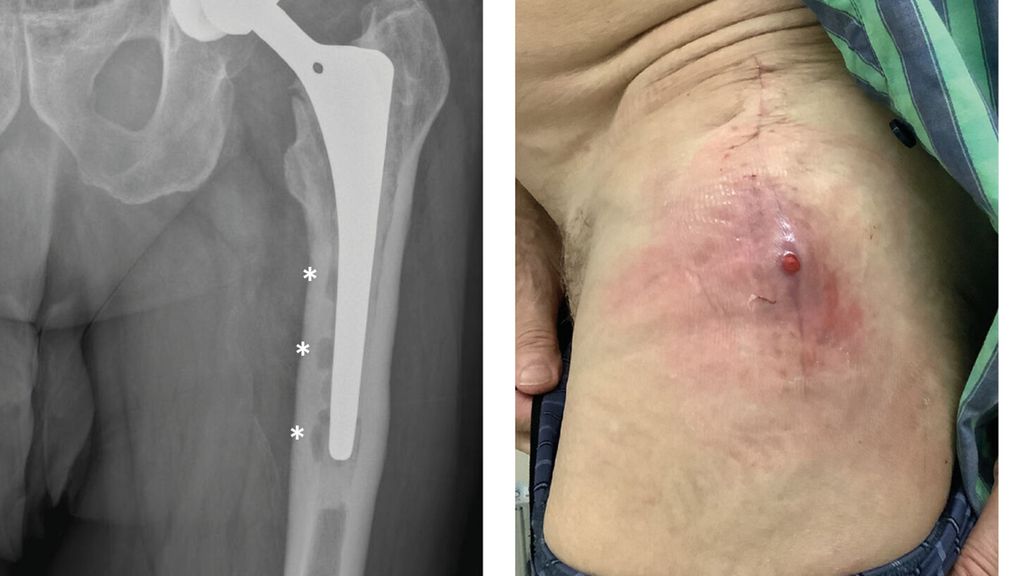

Abb. 1: Patient mit chronischer Hüftendoprotheseninfektion. Radiologisch zeigen sich infektionsbedingte periprothetische Osteolysen (*, a) und klinisch imponiert eine kutane Fistel (b).

Diagnostik der PPI

Anhand der klinischen Zeichen und der Symptomdauer unterscheidet man zwischen akuter und chronischer PPI. Die akute PPI ist durch eine kurze Symptomdauer (<3 Wochen) charakterisiert. Sie tritt entweder in der frühen (<4 Wochen) Phase nach endoprothetischem Gelenkersatz (akute postoperative PPI) oder aber verzögert (>4 Wochen, ggf. erst mehrere Jahre) nach Endoprothesenimplantation im Rahmen einer hämatogenen Streuung eines endoprothesenfernen Infektionsherdes (akute hämatogene PPI) auf. Typischerweise imponieren hier lokale Infektionszeichen wie Schmerzen, Schwellung, Rötung, Überwärmung oder eine prolongierte Wundsekretion (>7 Tage). Die Unterscheidung zwischen akuter und chronischer PPI basiert auf den Eigenschaften des bakteriellen Biofilms. Beim Vorliegen einer akuten PPI ist von einem unreifen bakteriellen Biofilm auf der Endoprothesenoberfläche auszugehen. Bei der chronischen PPI (>4 Wochen postoperativ) mit längerer Symptomdauer (>3 Wochen) liegt hingegen ein potenziell reifer Biofilm vor. Die klinischen Symptome sind in der Regel weniger ausgeprägt. Jedoch kann das Vorliegen einer kutanen Fistel oder von radiologischen Zeichen der Endoprothesenlockerung auf eine chronische Infektion hinweisen (z. B. Abb. 1).